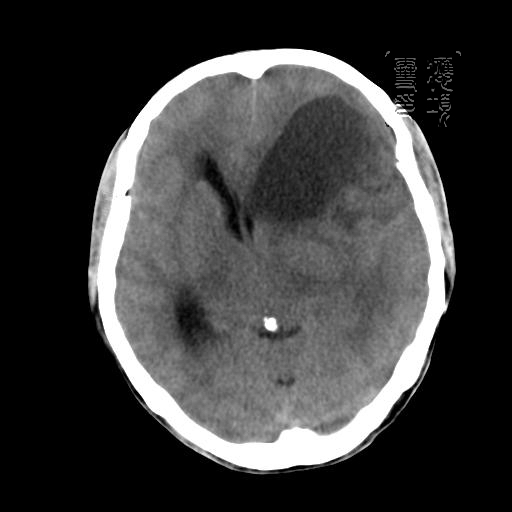

m 52y

二月前癫痫入院, 无既往史,现头痛、呕吐、视力减退、复视行ct平扫及增强检查。

见环形,结节样强化,考虑囊性星型细胞瘤。

考虑囊性星型细胞瘤,ct征象大囊小结节.

左额叶囊实性占位,以囊性为主,并见明显强化不规则壁结节,占位效应明显,首先考虑是囊性星形细胞瘤.

从发病部位及年龄都不考虑是血管母细胞瘤,还有可能是胶质瘤.

环形强化,壁薄、完整、光滑,而且有结节强化,个人考虑不典型脑脓肿多!